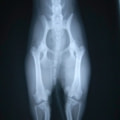

■ 症例24 キャバリア 7か月

左右膝蓋骨内方脱臼(左:グレードⅣ 右:グレードⅢ)

以前から左右後肢の跛行が認められ、整形外科学的検査・レントゲン検査により左右の膝蓋骨脱臼が認められた。症状が重度である左膝の膝蓋骨脱臼整復術を行った。外科手技は縫工筋及び内側広筋の解放、脛骨粗面の外側転位、滑車ブロック形造溝術、内外側関節方の縫縮を実施した。術後一か月時点で、左の膝蓋骨は安定しており経過は良好である。

■ 症例20 ポメラニアン 8ヶ月 1.8kg

左右膝蓋骨脱臼 グレードⅢ

2ヶ月前から間欠的跛行が認められ、両膝の膝蓋骨脱臼整復術を行った。